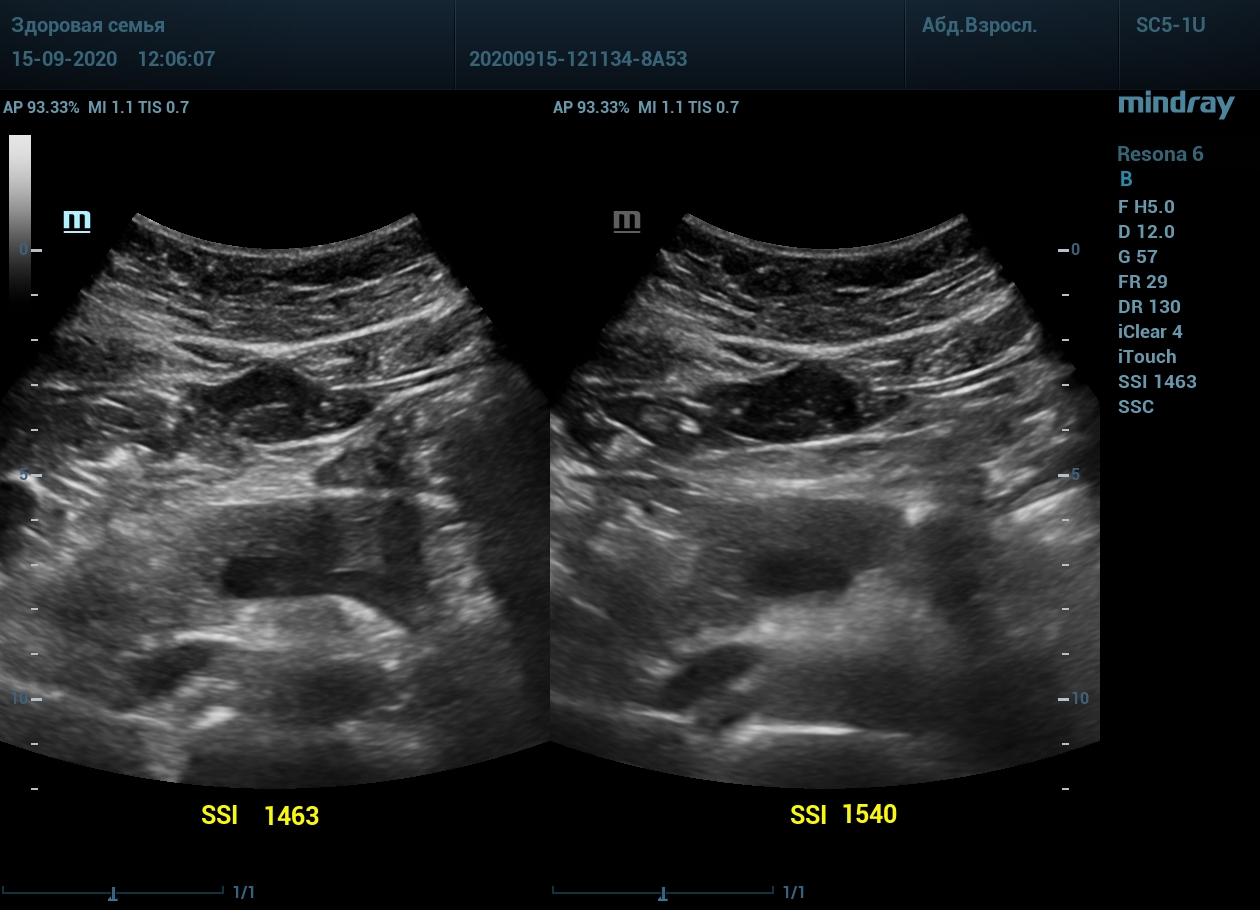

Примеры изображений:

2. Абдоминальный доступ левой почки. После калибровки скорости, дальний от датчика контур почки становится четким и контрастным.